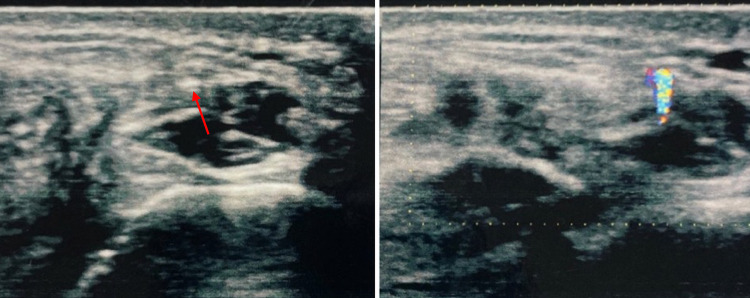

Fig. 4.

A 45-year-old woman underwent surgery and was later admitted to our hospital reporting discomfort at the level of the sutured wound. The polyethylene threads were clearly visible at US grayscale imaging whereas the small FB was not. In this case both sutures and FB produced TA. The localized FB was subsequently surgically removed, resolving the patient's symptoms

Fig. 5.

Case 5. A 47-year-old man was admitted to our hospital with pain in the palm of his right hand, which had suffered injury. The patient reported that he had cut his hand on a glass jar. Once the wound had healed, the patient began to experience pain which increased when subject to pressure. US grayscale image showed no sign of an FB, which was clearly visible at CDUS thanks to the presence of TA at the base of the fifth finger